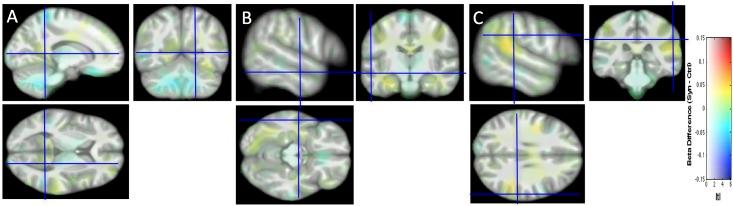

Several publications have reported structural changes in the brain of synesthetes compared to controls, either local differences or differences in connectivity. In the present study, we pursued this quest for structural brain differences that might support the subjective experience of synesthesia. In particular, for the first time in this field, we investigated brain folding in comparing 45 sulcal shapes in each hemisphere of control and grapheme-color synesthete populations. To overcome flaws relative to data interpretation based only on p-values, common in the synesthesia literature, we report confidence intervals of effect sizes. Moreover, our statistical maps are displayed without introducing the classical, but misleading, p-value level threshold. We adopt such a methodological procedure to facilitate appropriate data interpretation and promote the "New Statistics" approach. Based on structural or diffusion magnetic resonance imaging data, we did not find any strong cerebral anomaly, in sulci, tissue volume, tissue density or fiber organization that could support synesthetic color experience. Finally, by sharing our complete datasets, we strongly support the multi-center construction of a sufficient large dataset repository for detecting, if any, subtle brain differences that may help understanding how a subjective experience, such as synesthesia, is mentally constructed.

一些出版物报道了与对照组相比,联觉者大脑的结构变化,无论是局部差异还是连接差异。在本研究中,我们追寻这些可能支持联觉主观体验的结构脑差异。特别是,我们首次在这个领域比较了对照组和字母-颜色联觉者群体的每侧半球的 45 个脑沟形状,以研究脑折叠。为了克服仅基于 p 值的数据分析中存在的缺陷,这种方法在联觉文献中很常见,我们报告了效应大小的置信区间。此外,我们的统计映射是在不引入经典但具有误导性的 p 值水平阈值的情况下显示的。我们采用这种方法来促进适当的数据解释并推广“新统计学”方法。基于结构或扩散磁共振成像数据,我们没有发现任何强烈的大脑异常,无论是在脑沟、组织体积、组织密度还是纤维组织方面,这些都可以支持联觉颜色体验。最后,通过共享我们的完整数据集,我们强烈支持建立一个足够大的多中心数据集存储库,以检测任何可能有助于理解像联觉这样的主观体验是如何在心理上构建的细微大脑差异。